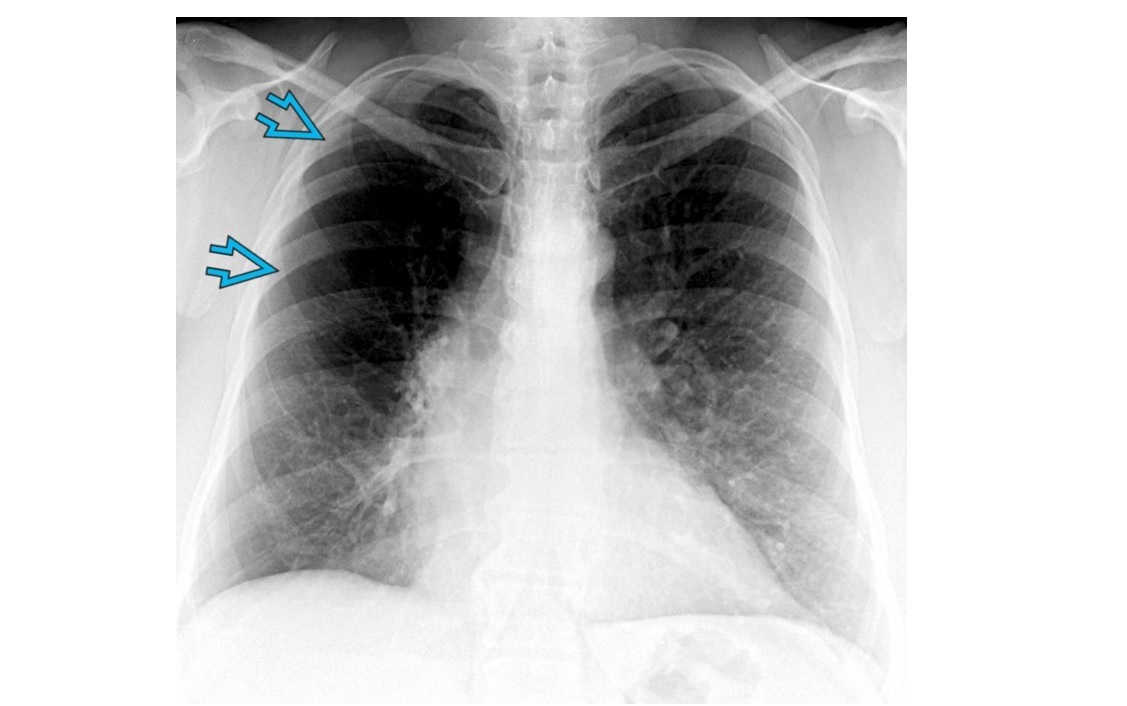

MAC

Tree in bud - terminal bronchiole filled with radiopaque material

cylindric bronchiectasis

clasically right middle lobe or lingula (aka lady windermere syndrome)

Other causes/areas of lung